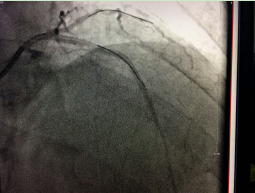

???我院成功開展市屬醫(yī)院首例冠狀動(dòng)脈內(nèi)膜旋磨術(shù)???? 在心臟血管內(nèi)開“隧道”,用高速旋轉(zhuǎn)的鉆石磨頭將堵塞心臟血管的鈣化斑塊磨碎,以此打通血管進(jìn)行冠心病的介入治療,這看起來像科幻電影里的場(chǎng)面,在我院實(shí)現(xiàn)。近日,我院完成了全市市屬醫(yī)院首例冠狀動(dòng)脈內(nèi)膜旋磨手術(shù),成功開通了血管,解除了患者長(zhǎng)期存在的胸悶...